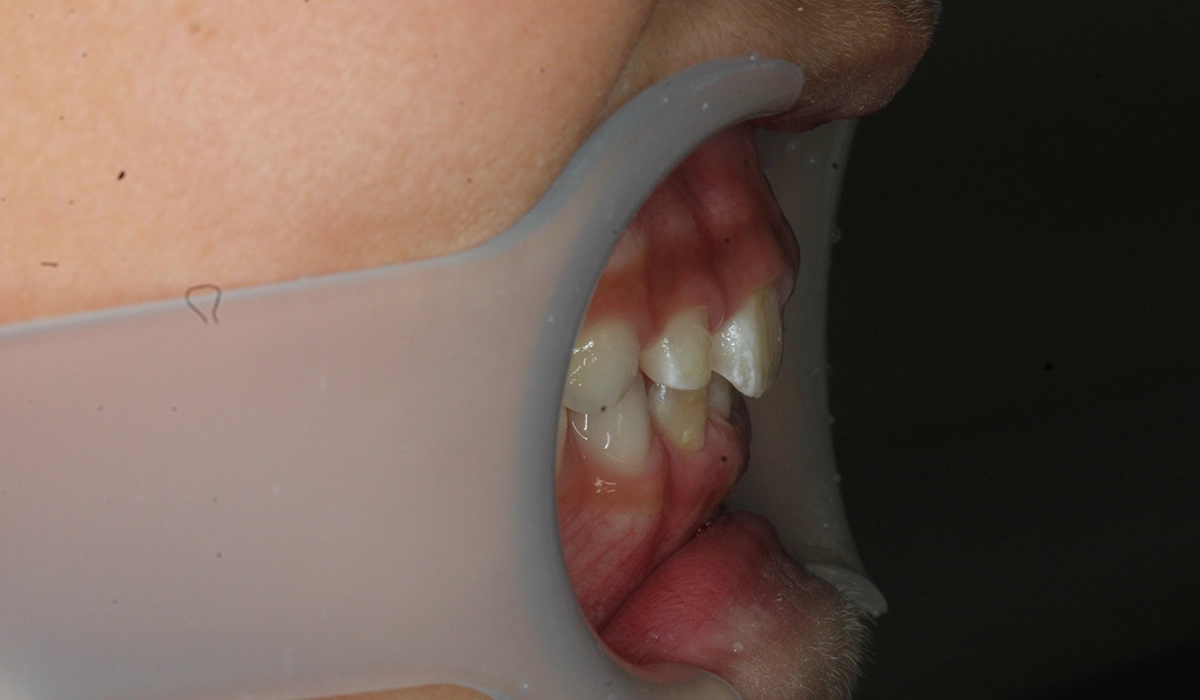

術前:右側

術後:右側